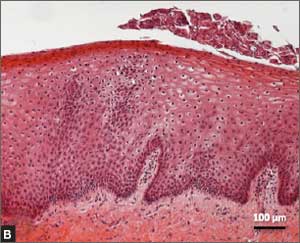

Recently published histology data highlight significant changes 1 month after fractional CO2 laser treatment that included a much thicker epithelium with wide columns of large epithelial cells rich in glycogen.21 Also noted was a significant reorganization of connective tissue, both in the lamina propria and the core of the papillae (FIGURES 1 and 2).

FIGURE 1: Early-stage vaginal atrophy

This histologic preparation of vaginal mucosa sections reveals untreated early-stage vaginal atrophy (A), with thinning epithelium and the presence of papillae, and the same mucosa 1 month after treatment with fractional CO2 laser therapy (B). Reprinted with permission from DEKA M.E.L.A. Srl (Calenzano, Italy) and Professor A. Calligaro, University of Pavia, Italy.